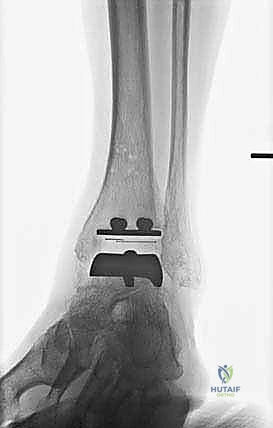

تُعد هذه الجراحة من أروع وأدق الإجراءات في عالم جراحة العظام. يقوم الأستاذ الدكتور محمد هطيف وفريقه الطبي في صنعاء بتنفيذها وفق بروتوكول عالمي صارم لضمان نسب نجاح تقارب 100٪. فيما يلي تفصيل دقيق لخطوات العملية، مدعوماً بالصور من داخل غرفة العمليات.

تعتمد دقة الجراحة على المحاذاة الصحيحة. يتم استخدام أجهزة توجيه متطورة (Jigs) تثبت على عظمة الساق باستخدام دبابيس معدنية. يتم التحقق من صحة الزوايا والمحاور باستخدام جهاز الأشعة السينية المباشر داخل غرفة العمليات (C-arm Fluoroscopy). يضمن الدكتور هطيف أن يكون القطع موازياً للأرض تماماً عند وقوف المريض.